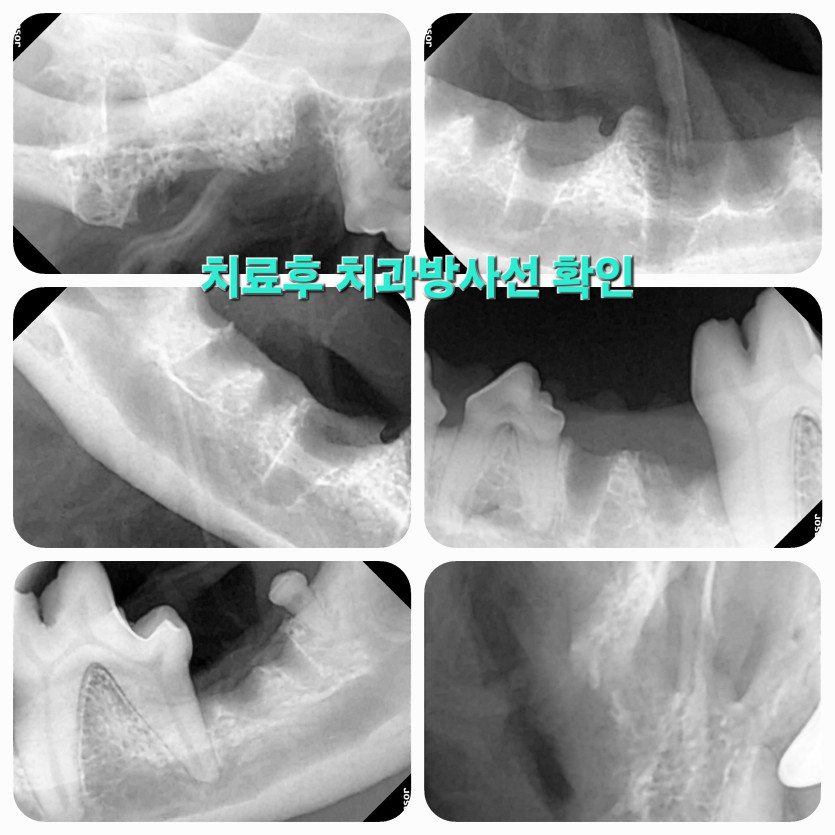

정확한 진단에 강아지를 진심으로 사랑하시는게 마음 깊이 와닿아서 믿고 맡길 수 있었어요.

의사선생님은 초코의 상태를 정확히 진단하시고 아이가 더 이상 아프지 않게 치료해줬어요.

치료 후 점점 회복중인 초코를 보며 의료진분들께 너무 감사드립니다.